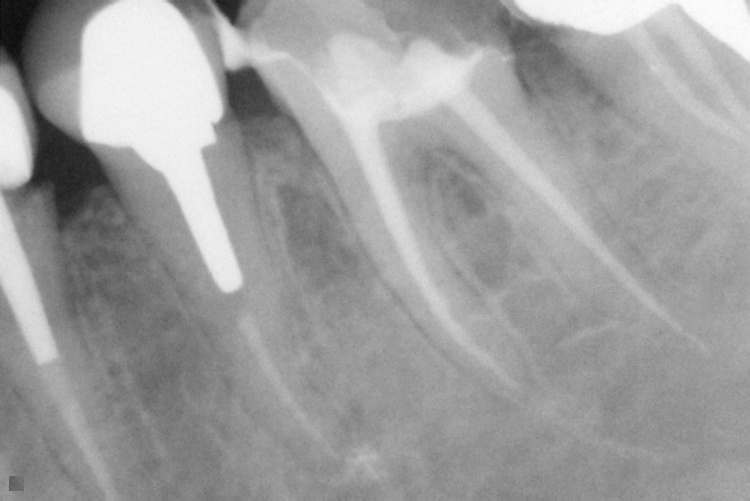

Name Last modified Size Description Parent Directory - IO000001.jpg 2020-07-28 14:20 84K IO000002.jpg 2020-07-28 14:20 82K IO000003.jpg 2020-07-28 14:20 85K IO000004.jpg 2020-07-28 14:20 82K IO000005.jpg 2020-07-28 14:20 84K